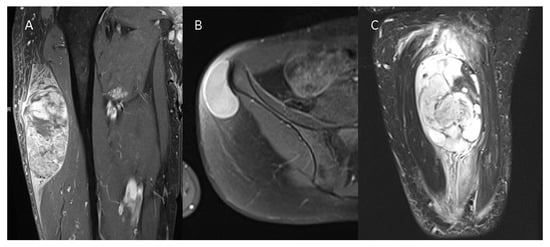

2.2. Image Analysis

3.2. Conventional Imaging Features